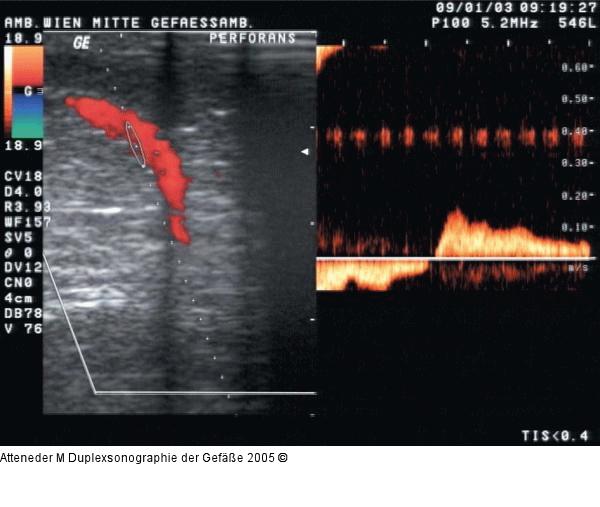

Abbildung 18: Duplexsonographie - Perforansinsuffizienz Dopplerkurve einer insuffizienten Vena perforans, bei distaler Kompression Flußumkehr in der Perforansvene |

Abbildung 18: Duplexsonographie - Perforansinsuffizienz

Dopplerkurve einer insuffizienten Vena perforans, bei distaler Kompression Flußumkehr in der Perforansvene |